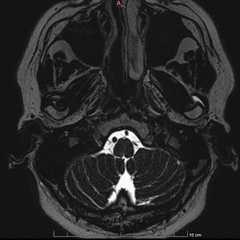

※ 記事半ばに脳のMRI写真が出てきます。苦手な方はご注意ください

顔面神経麻痺は「顔がまがってきた」、「眼が閉じにくい」、「水が口からこぼれる」、「口の動きが悪くなる」など、顔の筋肉が動きづらくなる病気です。